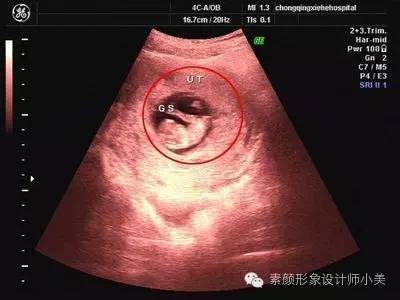

8周胎儿发育

第8周的胚胎大约有16毫米长,看上去挺像颗葡萄的。这时胚胎像跳动的豆子一样开始有运动。因为骨髓还没有成形,现在由肝脏来生产大量的红细胞,直到骨髓成形后去接管肝脏的作用。虽然身体很小但是心脏和大脑已发育得非常复杂了,胚胎的器官已经开始有明显的特征,各个不同的器官开始劳碌地发育,手指和脚趾间看上去有少量的蹼状物。牙和腭也开始发育,耳朵也在继续发育,胎儿的皮肤犹如纸一样地薄,可以清晰的看到血管。虽然在子宫里面你觉得还是处于无声无息的状态,其实胎儿现在已经会在里面做一些踢腿、伸腿、抬手、移动双臂的小动作了。

第一次产检:

一般在孕期第8周-12周时要进行第一次正式产检,此时医院会给每位孕妇建立一个档案,记录你整个孕期每次身体检查情况。所以第一次产检也俗称为“建档”。第一次产检的项目通常包括问诊,测量体重和血压,听胎心,验尿,验血,检查子宫大小等。会因各医院安排的不同和孕妇的具体情况而在某些项目上大同小异。